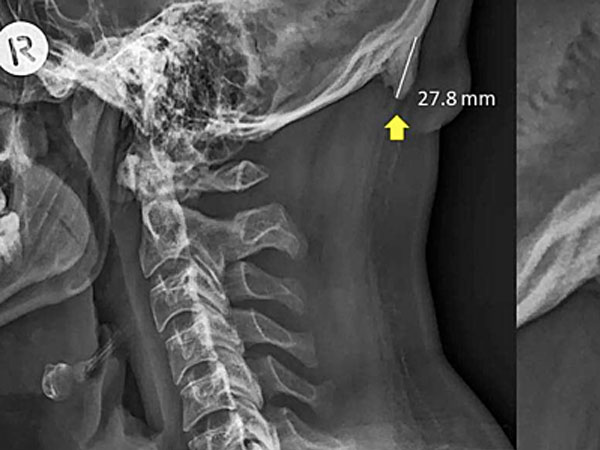

22/06/2019 01:07Hộp sọ 'mọc' gai nghi do nghiện điện thoại thông minh

Các nhà khoa học từ University of The Sunshine Coast (Australia) cho biết càng nhiều bệnh nhân trẻ đến bệnh viện với những chiếc gai nhỏ phía sau cổ. Thông thường, chúng có chiều dài khoảng 2,6 cm nhưng một số trường hợp có thể lên đến 3,1 cm.

Trên Scientific Reports, các nhà khoa học University of The Sunshine Coast cho biết hiện tượng hộp sọ "mọc" gai trên còn được gọi là đáy gai nhô bên ngoài vùng chẩm (EEOP), chủ yếu xuất hiện ở người già. Tuy nhiên, khảo sát trên 1.200 tình nguyện viên 18-86 tuổi cho thấy 33% bị EEOP, trong đó phần lớn thuộc nhóm nam giới 18-30 tuổi. Các nhà khoa học cho biết tình trạng này bắt đầu xuất hiện vào những năm 1990 và ngày càng phổ biến.

Hiện tại, các nhà khoa học chưa tìm ra được mối liên hệ chính xác nhưng cho rằng việc sử dụng các thiết bị điện tử ở tư thế sai dẫn đến tình trạng này. Ngồi hàng giờ với chiếc cổ bị quẹo hoặc cúi xuống quá thấp có thể gây áp lực cho nền sọ và cơ thể sẽ phản ứng lại bằng cách xuất hiện gai nhỏ để đỡ.